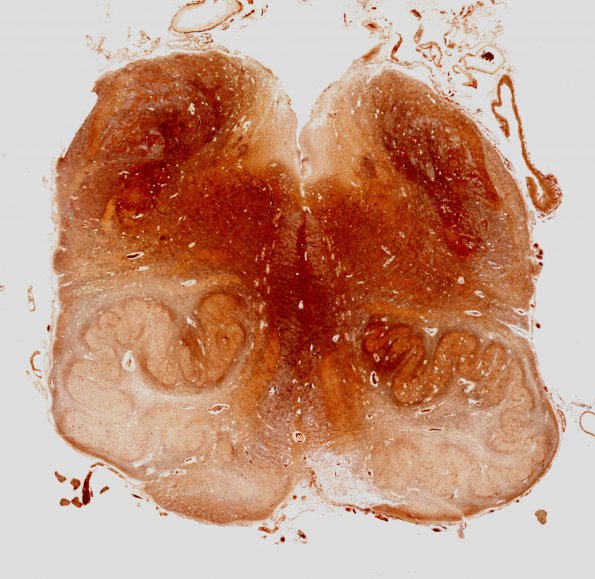

Washington University Experience | BASIC PROCESSES | Olivary Hyperplasia | 10E1 Infarcts, multiple, Olive HT (Case 12) Biels WM

10E1,2 Adjacent section of medulla stained for axons highlights the multivacuolated neurons and loss of axons in the pyramids.. (Bielschowsky silver stain)